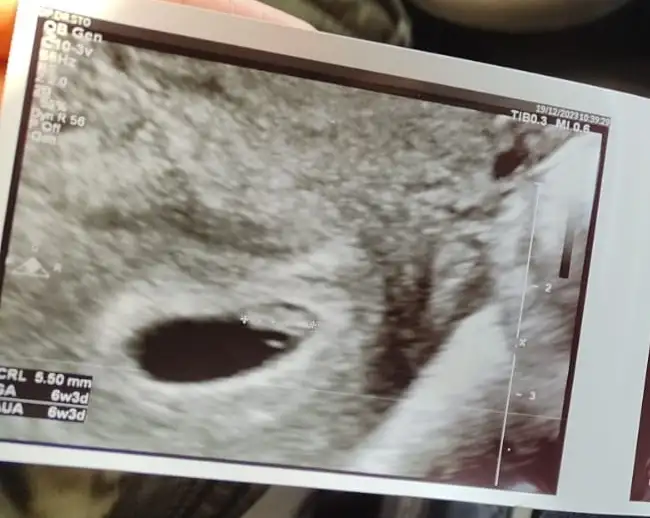

Karın ultrasonu ise erkek diyorum canım hayırlısı konumu değişede bilirT Tali89 merhabaaavalla müsait olursan bende merak ediyorum. 6+2 karından bakıldı çıktısı biraz parlak o yuzden videodan aldim fotoyuEki Görüntüle 3385719